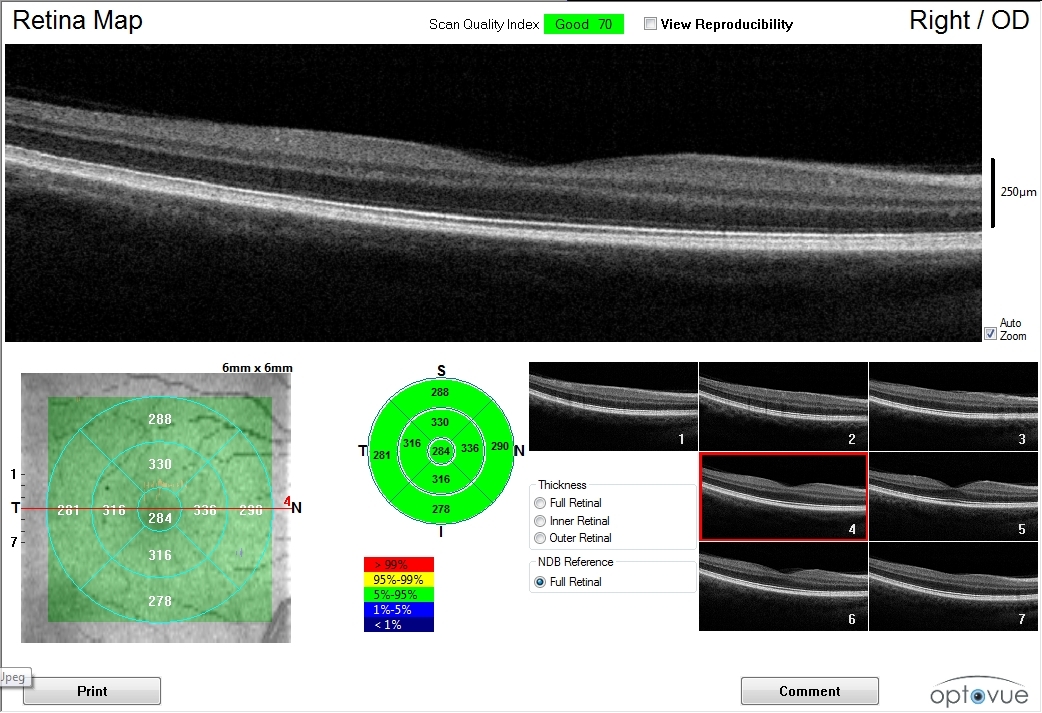

Optical Coherence Tomography (OCT) functions like an MRI for your eyes, creating detailed cross-sectional images of the retina. This technology detects microscopic changes in retinal layers years before symptoms develop, enabling early intervention for conditions like macular degeneration and glaucoma. When choosing an eye doctor in San Francisco, ask whether they use OCT imaging—it's a significant indicator of their commitment to comprehensive care.